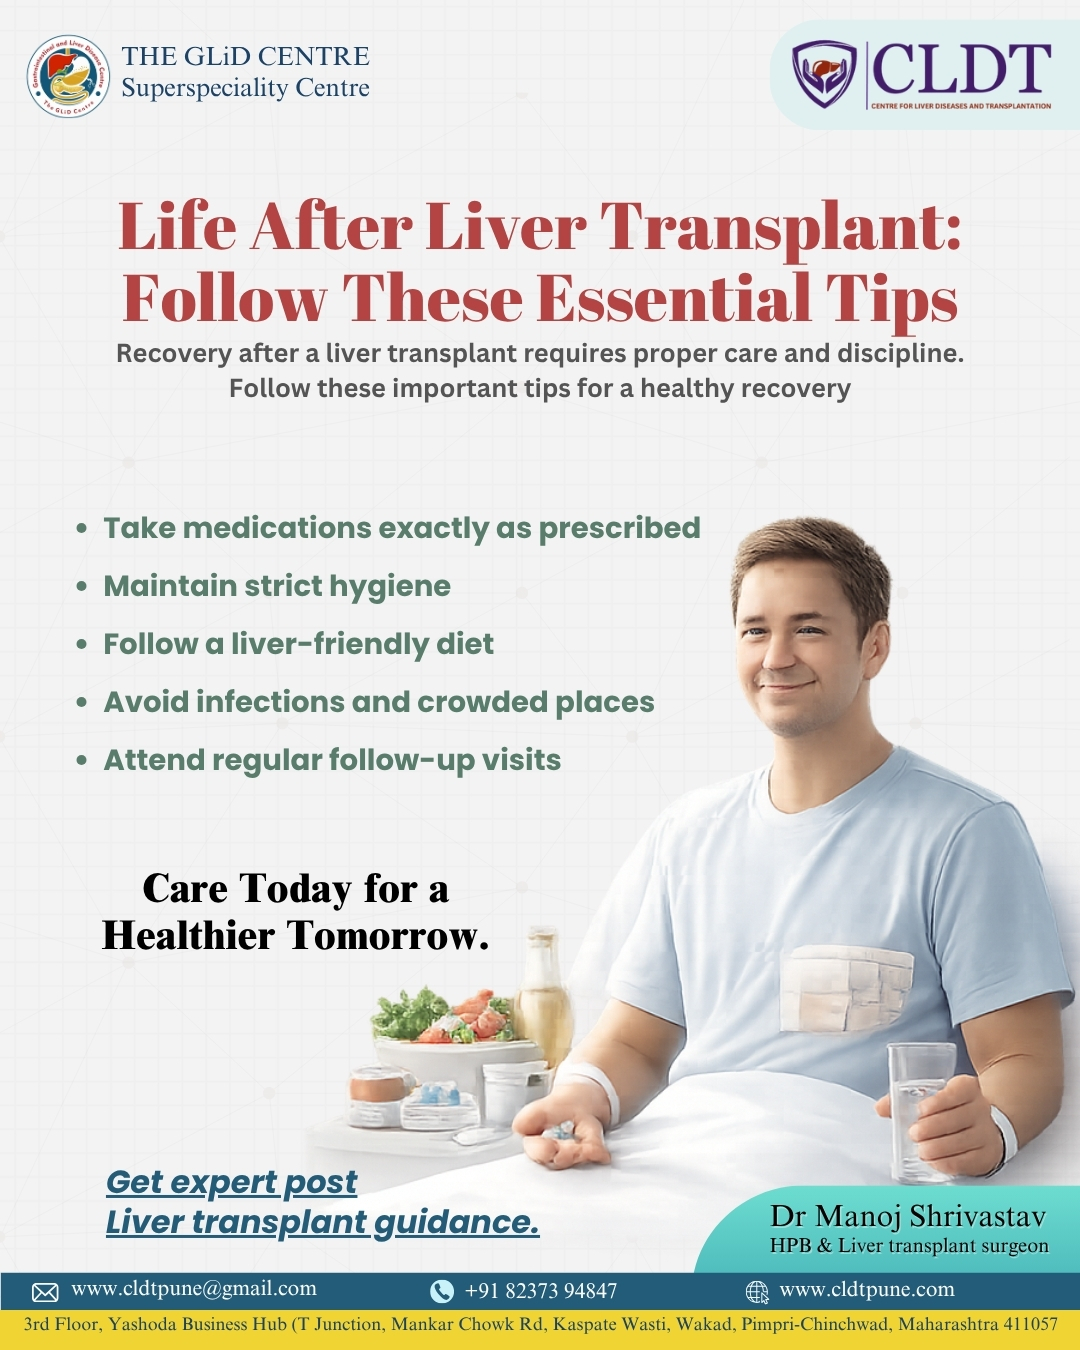

Elevated Liver Enzymes: Myth vs Fact –

By Dr. Manoj Shrivastav Liver Transplant Surgeon in Pune |...